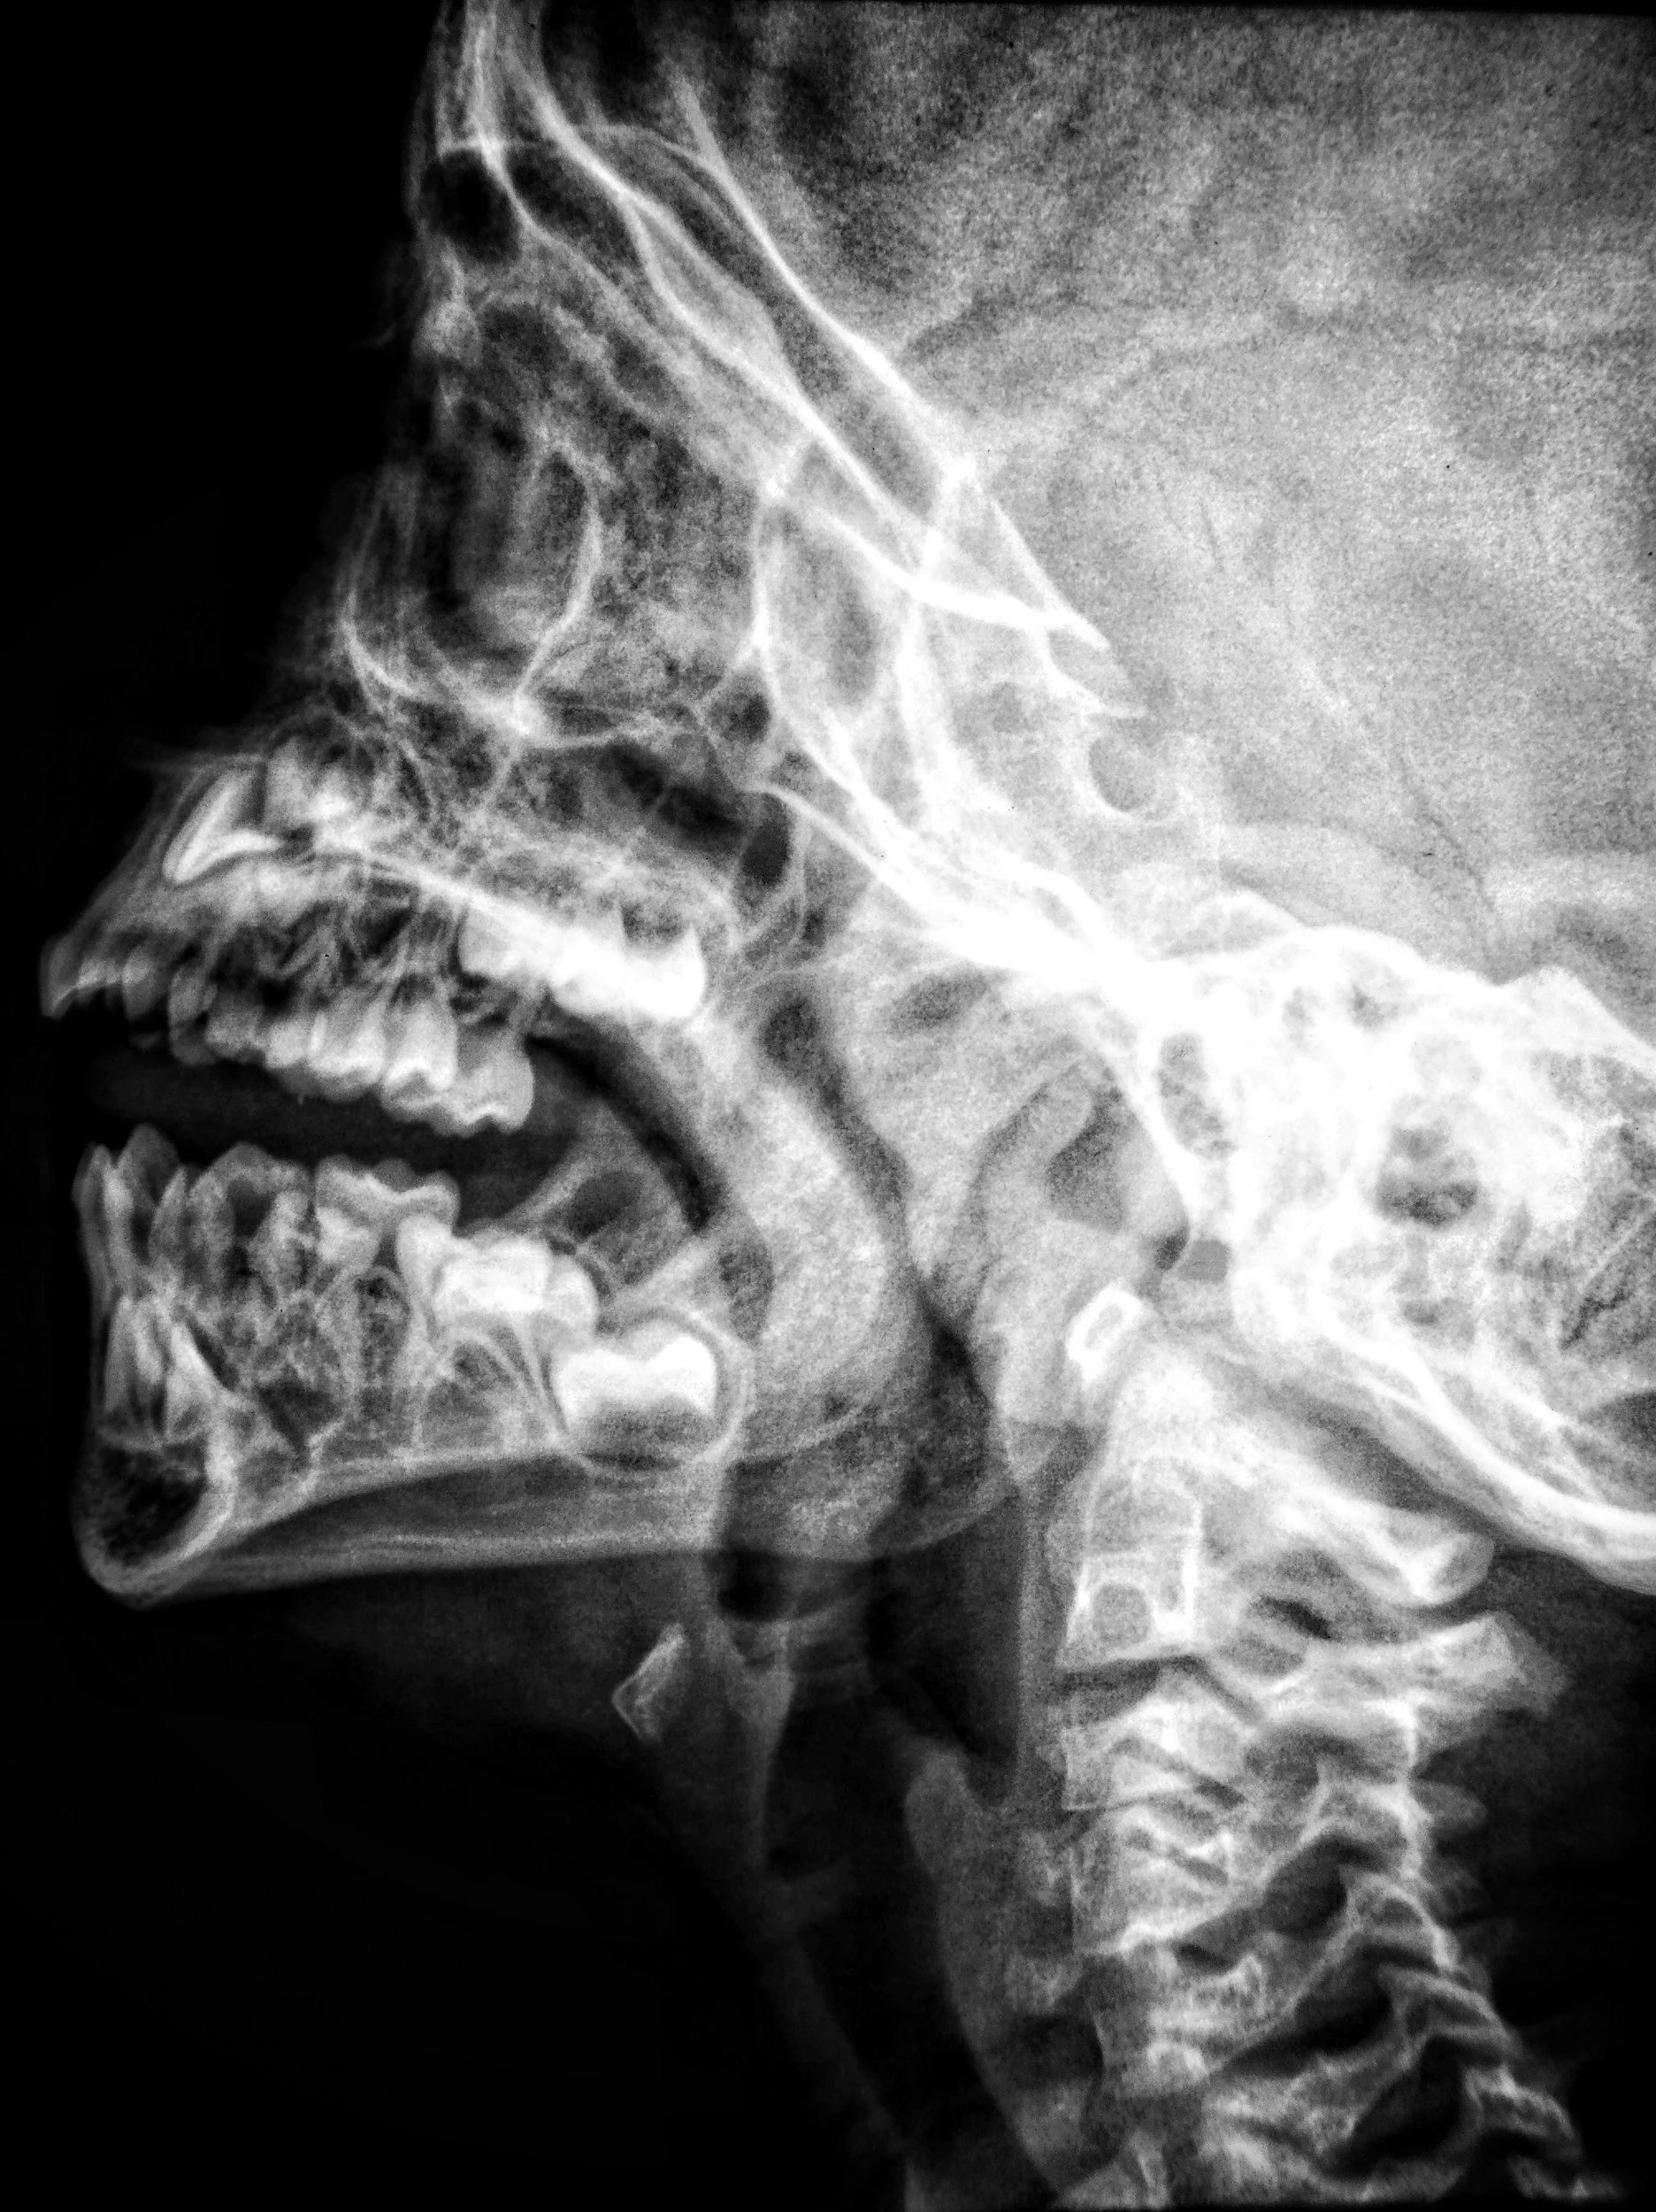

Con nuestros equipos podemos obtener imágenes panorámicas, de perfil y en 3 dimensiones con gran nitidez, gracias a su sistema innovador que sigue perfectamente la curva natural de tus dientes, consiguiendo ver toda tu boca de la forma más clara posible, enfocándonos solo en lo que realmente importa: diagnósticos mucho más precisos con la menor radiación necesaria.